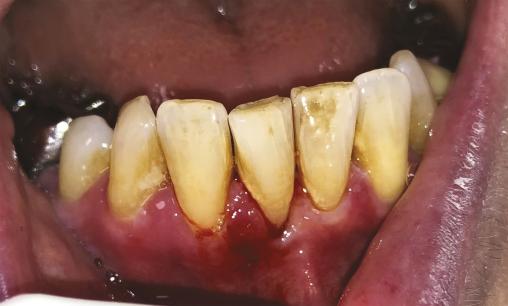

Une patiente de 61 ans consulte pour une gingivorragie diffuse persistante et douloureuse, ainsi que des ulcérations buccales récurrentes au cours des trois derniers mois. Ses antécédents médicaux comprennent une thyroïdectomie substituée par une hormonothérapie et un reflux gastro-œsophagien. On note l’absence d’intoxication alcoolo-tabagique. La patiente ne rapporte pas de modification récente de ses traitements, de son alimentation, de son dentifrice ou de ses habitudes de vie, ni de symptôme extra-oral. Malgré l’éviction des aliments acides tels que le citron ou le vinaigre, ses symptômes persistent. L’examen endobuccal révèle des lésions gingivales hyperkératosiques et érythémateuses, une lésion bulleuse gingivale (fig. 1 ) et plusieurs érosions (fig. 2 ) associées à une gingivite légère. Le signe de Nikolsky est positif, correspondant à l’érosion induite par un frottement sur une peau ou une muqueuse d’apparence saine, suggérant une maladie bulleuse. Aucune adénopathie cervicofaciale n’est objectivée lors de l’examen clinique.